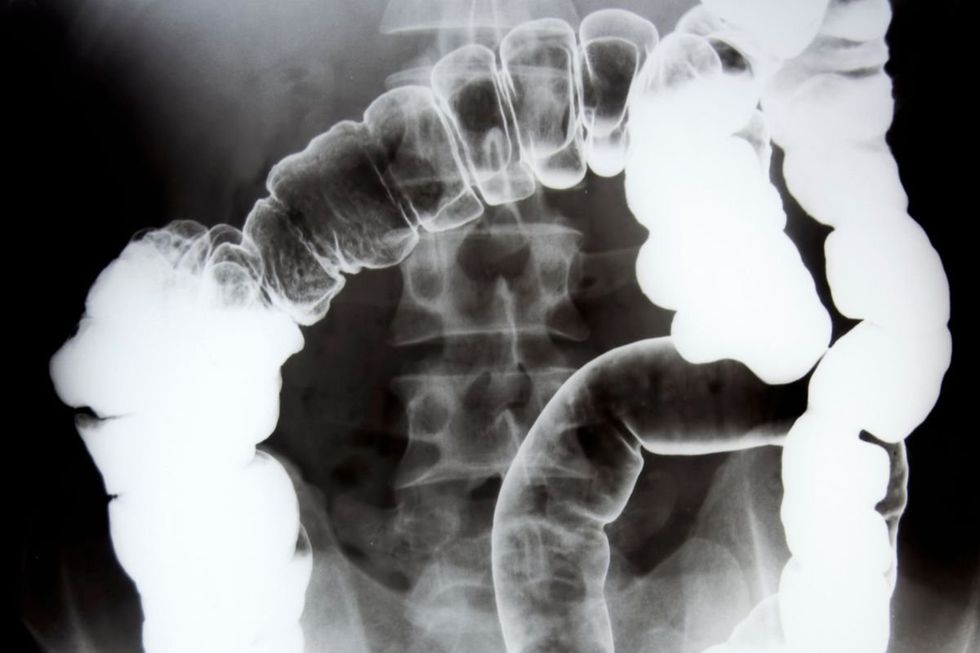

The symptoms of colon cancer overlap with those of many other minor ailments

|GETTY

Should results show that there is blood in the stools, patients are typically referred for either a colonoscopy or a CT scan.